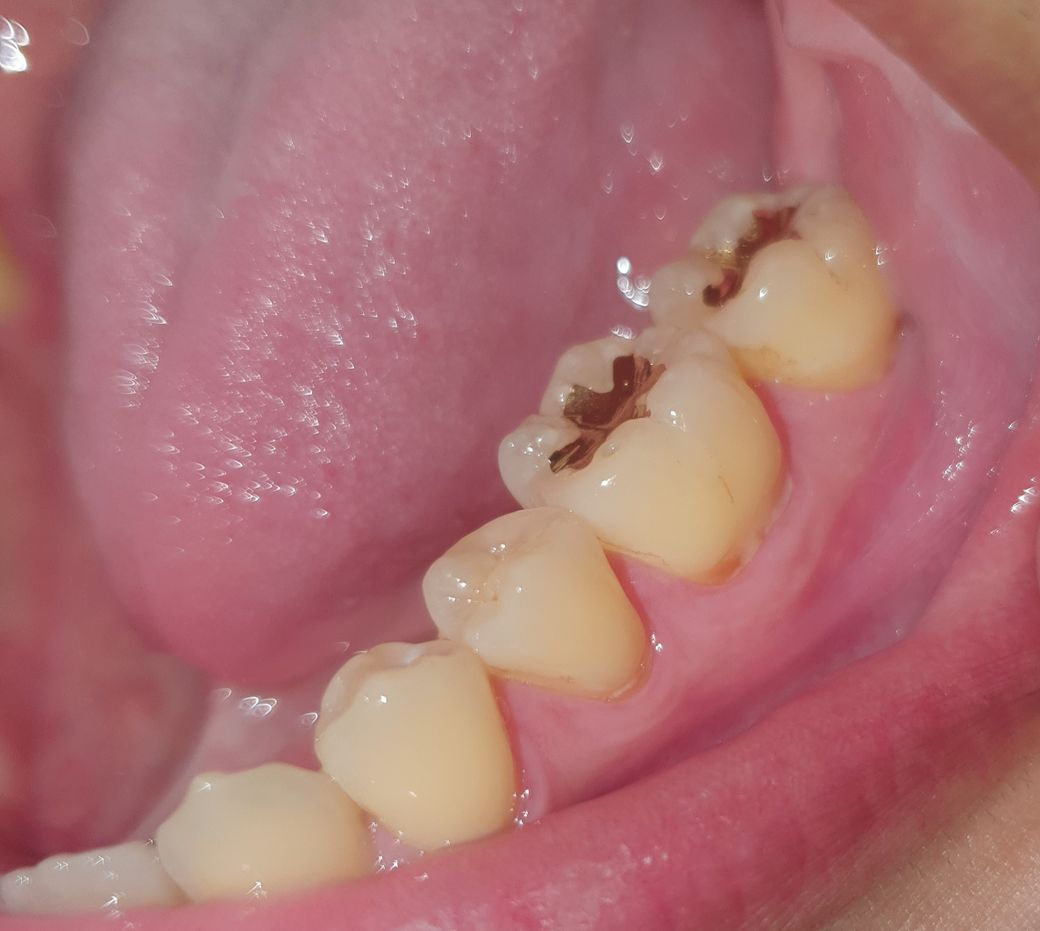

어금니들 잇몸 가까이 갈색 실금들 가 있는데 충치인가요?

저 갈색 실금들 있는 어금니들 다 충치인가요?

스케일링 받으면 없어질 줄 알았는데 그대로네요 😭

• 1번 째 사진

• 사진으로 봤을 경우에는 치아 표면에 착색이 된 것으로 보입니다 크게 문제를 발생시키진 않기 때문에 너무 걱정하지는 않으셔도 될 것으로 생각됩니다

• 실금처럼 보이는 것이라면 사진에 동그라미로 표시한 이 부분을 말씀하시는건가요?이건 아마 충치가 아니라 착색인 것 같아요. 저 착색은 스케일링하는 기구로도 지워질 것 같은데, 어떤 선생님들은 스케일링할 때 치석만 제거하고 착색은 제거안해주는 경우도 있긴하더라구요. 저 부분 제거가 안되는거냐고 물어보세요~그리고 혹시나 해서 말씀드리는건데 충치인지 아닌지 확인하는건 진료과목이 달라도 다 할 수 있으니까 편하게 문의하셔도 괜찮아요.

• 충치의 양상은 아니라고 보여집니다 스케일링으로도 지워지지 않는다면 잇몸치료에 쓰이는 큐렛이라는 기구로 긁어볼순 있을 것 같습니다

• 충치라기 보다는 치아가 변색이 된 곳이 곳곳에 보이고 치경부 마모도 약간 보입니다.

증상이 없으면 굳이 치료할 필요는 없어보입니다.